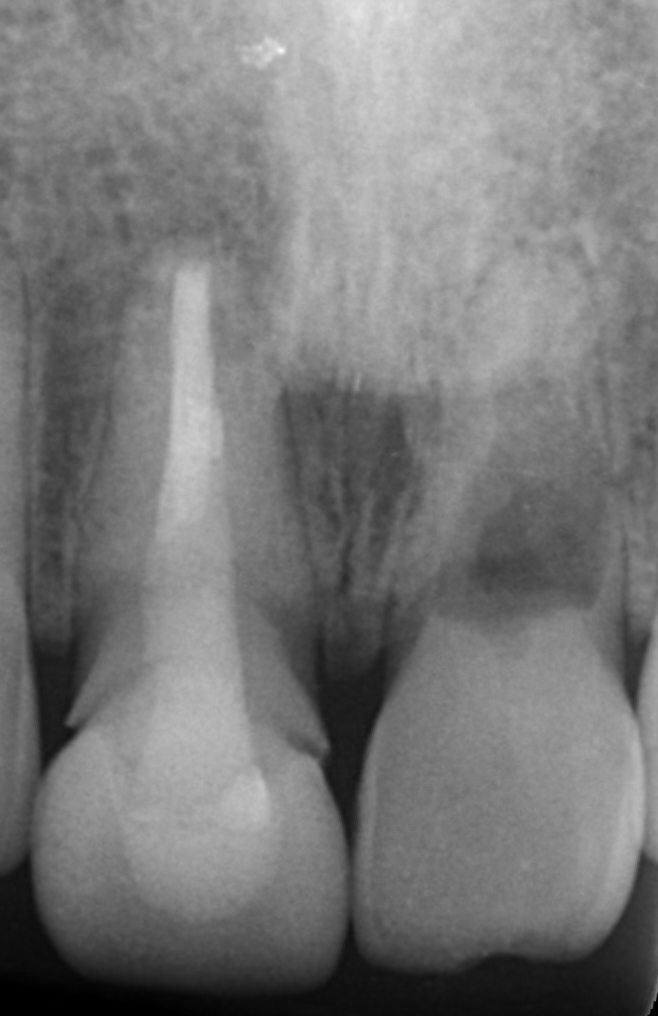

右上顎中切歯にレントゲン所見で僅かですが根尖部に限局した透過像と歯肉の腫れを認めました。

つまり、候補となりうる他の疾患との「鑑別」が重要になります。私が考えた鑑別診断は以下の2点ですが、結果として右上顎中切歯の根尖性歯周炎との診断の下、治療を開始いたしました。

VRF(垂直性歯根破折)との鑑別 レントゲン上で透過像が根尖部に限局している点、垂直性歯周ポケットを認めない点から、積極的に疑う所見がないと判断いたしました。ただしVRFは根尖側からクラックが入ることが多いため、最終的には被せ物を外してマイクロスコープを用い、視診で破折を確認します。(※CTやレントゲンでは完全破折以外は確定診断が難しい場合があります。)

隣在歯の根尖性歯周炎の可能性 根尖性歯周炎は、歯髄組織が壊死を起こしているか、過去に根管治療を施行された「失活歯」にしか発症しません。今回の症例では、右上顎側切歯および左上顎中切歯にEPT(電気歯髄診)で生活反応を示したため、消去法で原因歯は過去に根管治療を施行されている「右上顎中切歯」のみとなります。

ここで、正確な診断がいかに大切かを示す別の症例を供覧いたします。 レントゲン上では左上顎側切歯の根尖部に大きな透過像を認め、前医では「抜歯してインプラント」と言われていたケースです。

しかし実際に診査診断をしてみると、左上顎側切歯はEPT陽性の「生活歯」でした。つまり、透過像の原因はこの歯ではなかったのです。結果的に左上顎中切歯の再精密根管治療を行うことで透過像の改善を認めました。もし側切歯を抜歯していたら……と思うと、患者様にセカンドオピニオンの発想がなければ大変悲しい結末となっておりました。